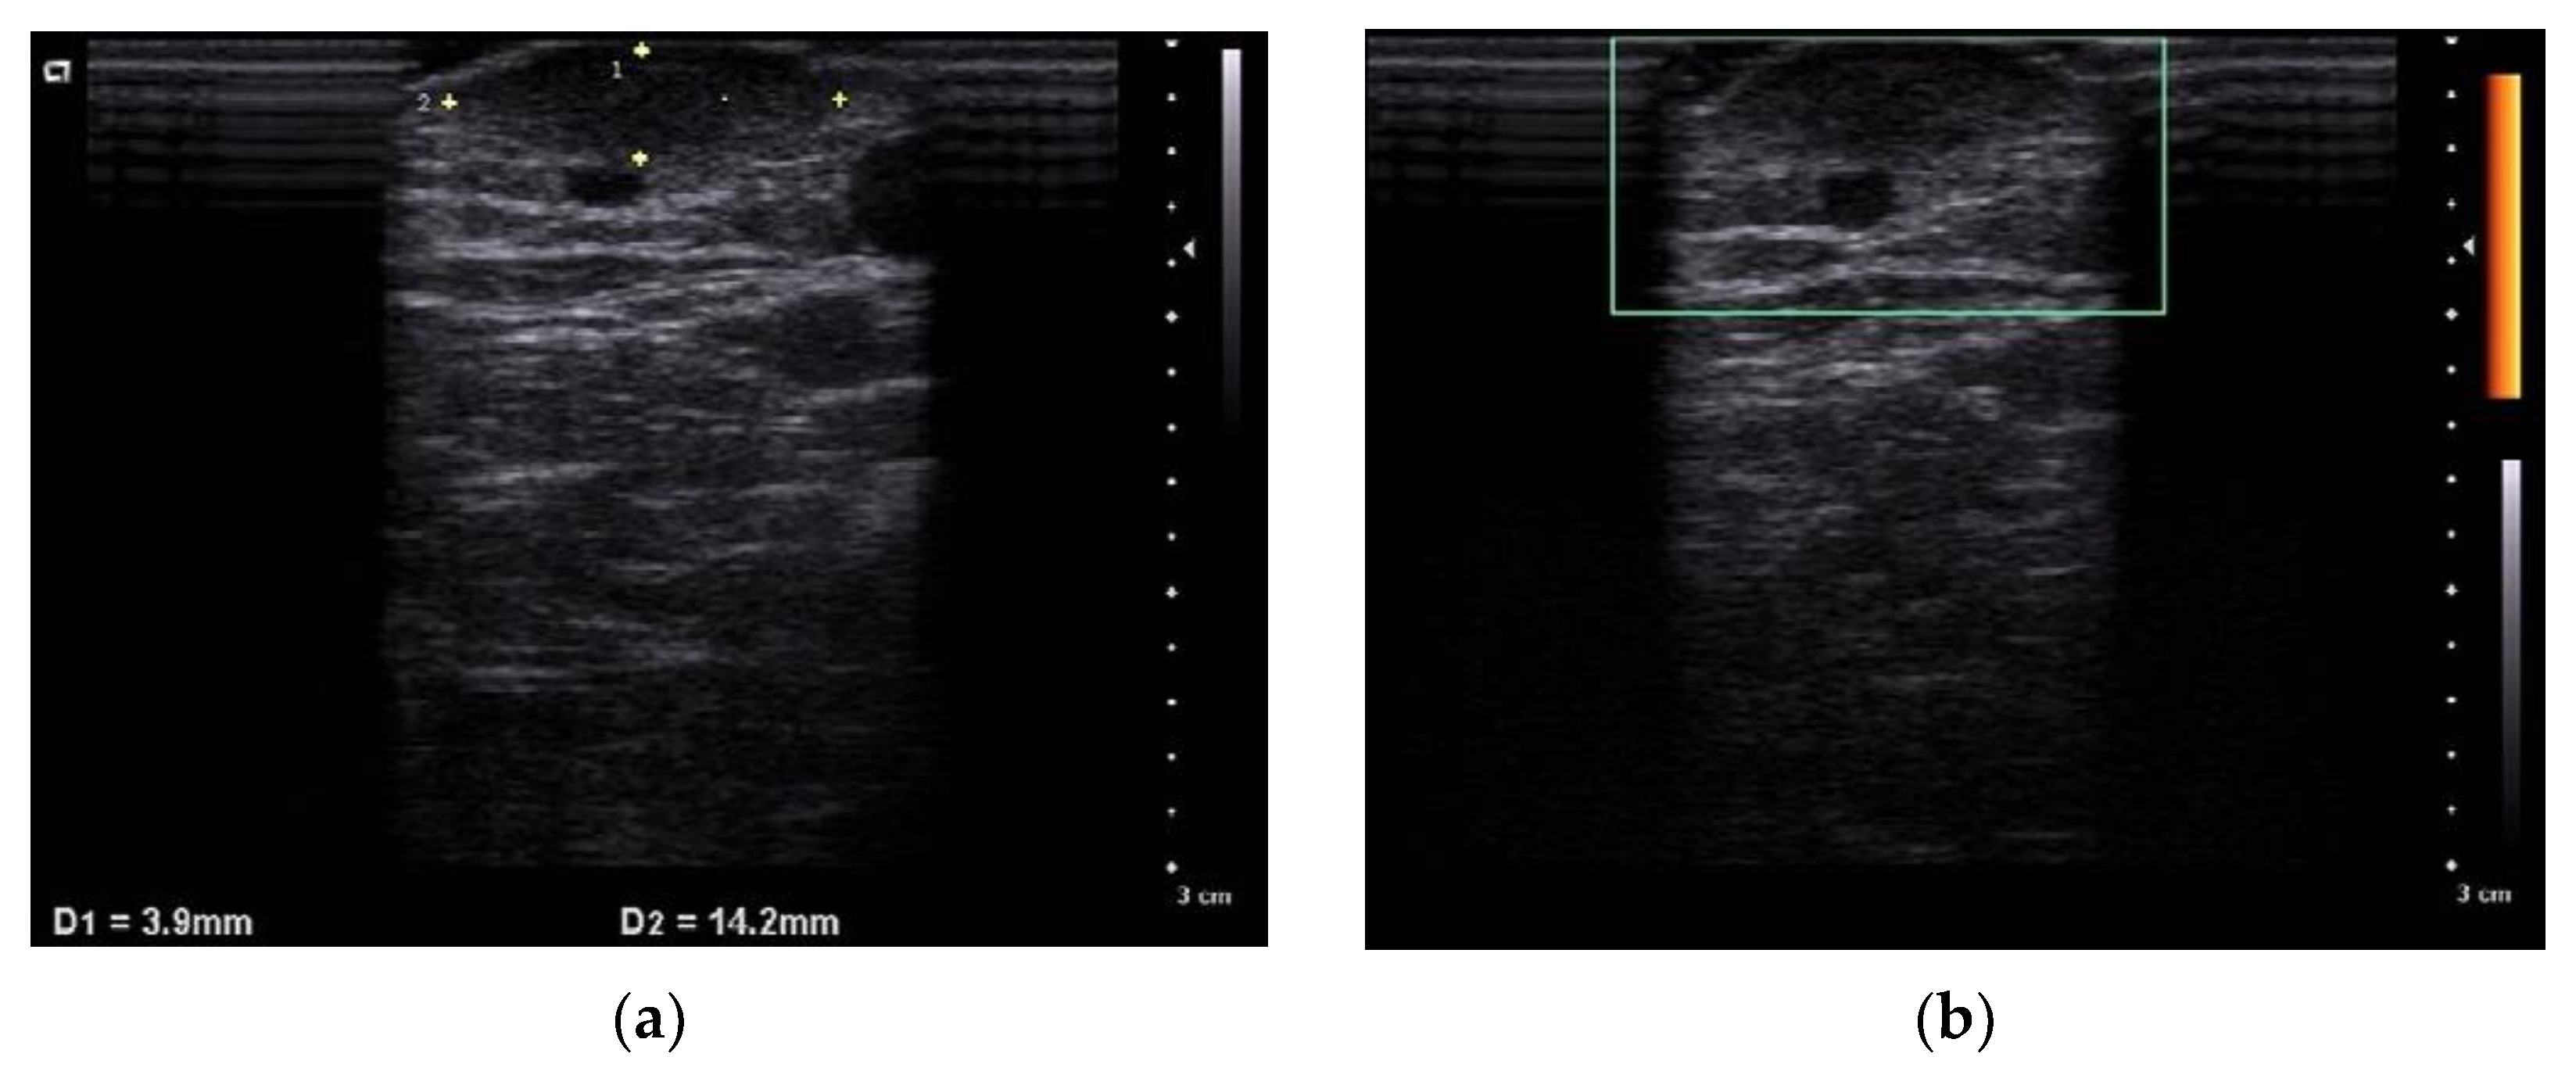

2.1. Case 1